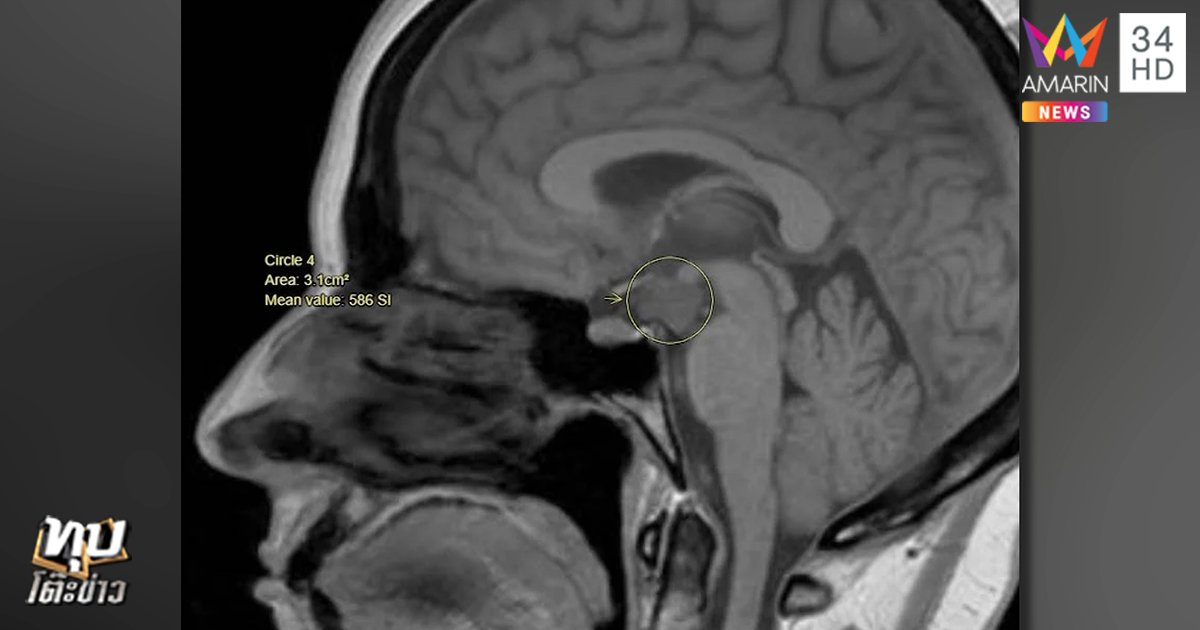

ปรากฏว่าหมอวินิจฉัยว่า น้องเป็นโรคเนื้องอกหัวเราะ จากการตรวจคลื่นสมองพบว่ามีเนื้องอกอยู่ที่บริเวณแกนกลางของสมอง จึงไปกดทับเส้นประสาทส่วนที่ทำให้หัวเราะและชักเกร็งและกระตุก